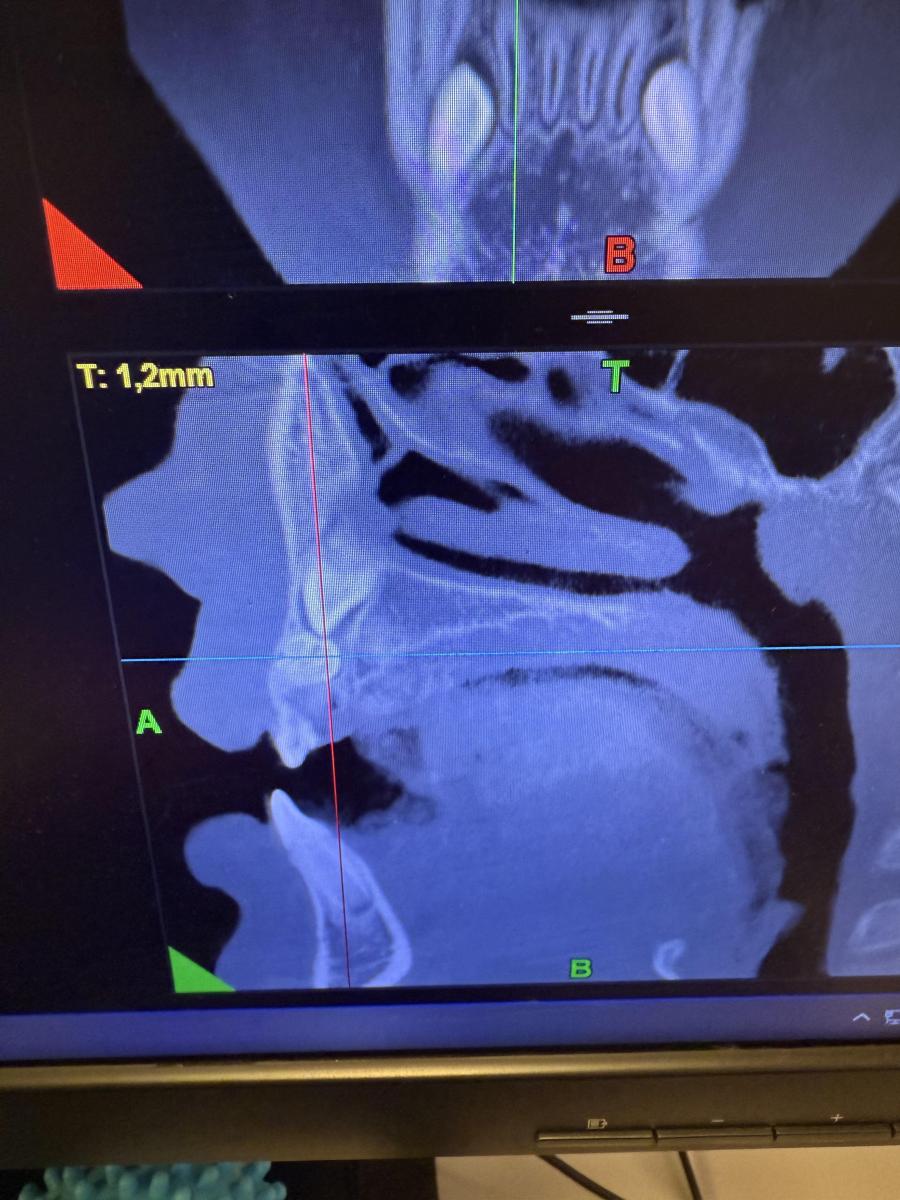

Здравствуйте, Ребекку 7 лет. Отсутствуют нижние зачатки 5 зубов. Верхний зачаток пятерки в недоразвитом состоянии и перевернут . Что с ним будет? Возможно ли что вырастет как надо? И основной вопрос- верхний клык (снимок прилагаю) между молочным и коренным обнаружено какое-то образование- это лишний зуб? Как его удалять? Вырывать молочный клык сейчас , далее удалять лишний и уже после ждать прорезывания постоянного? Или ждать пока молочный сам выпадет?